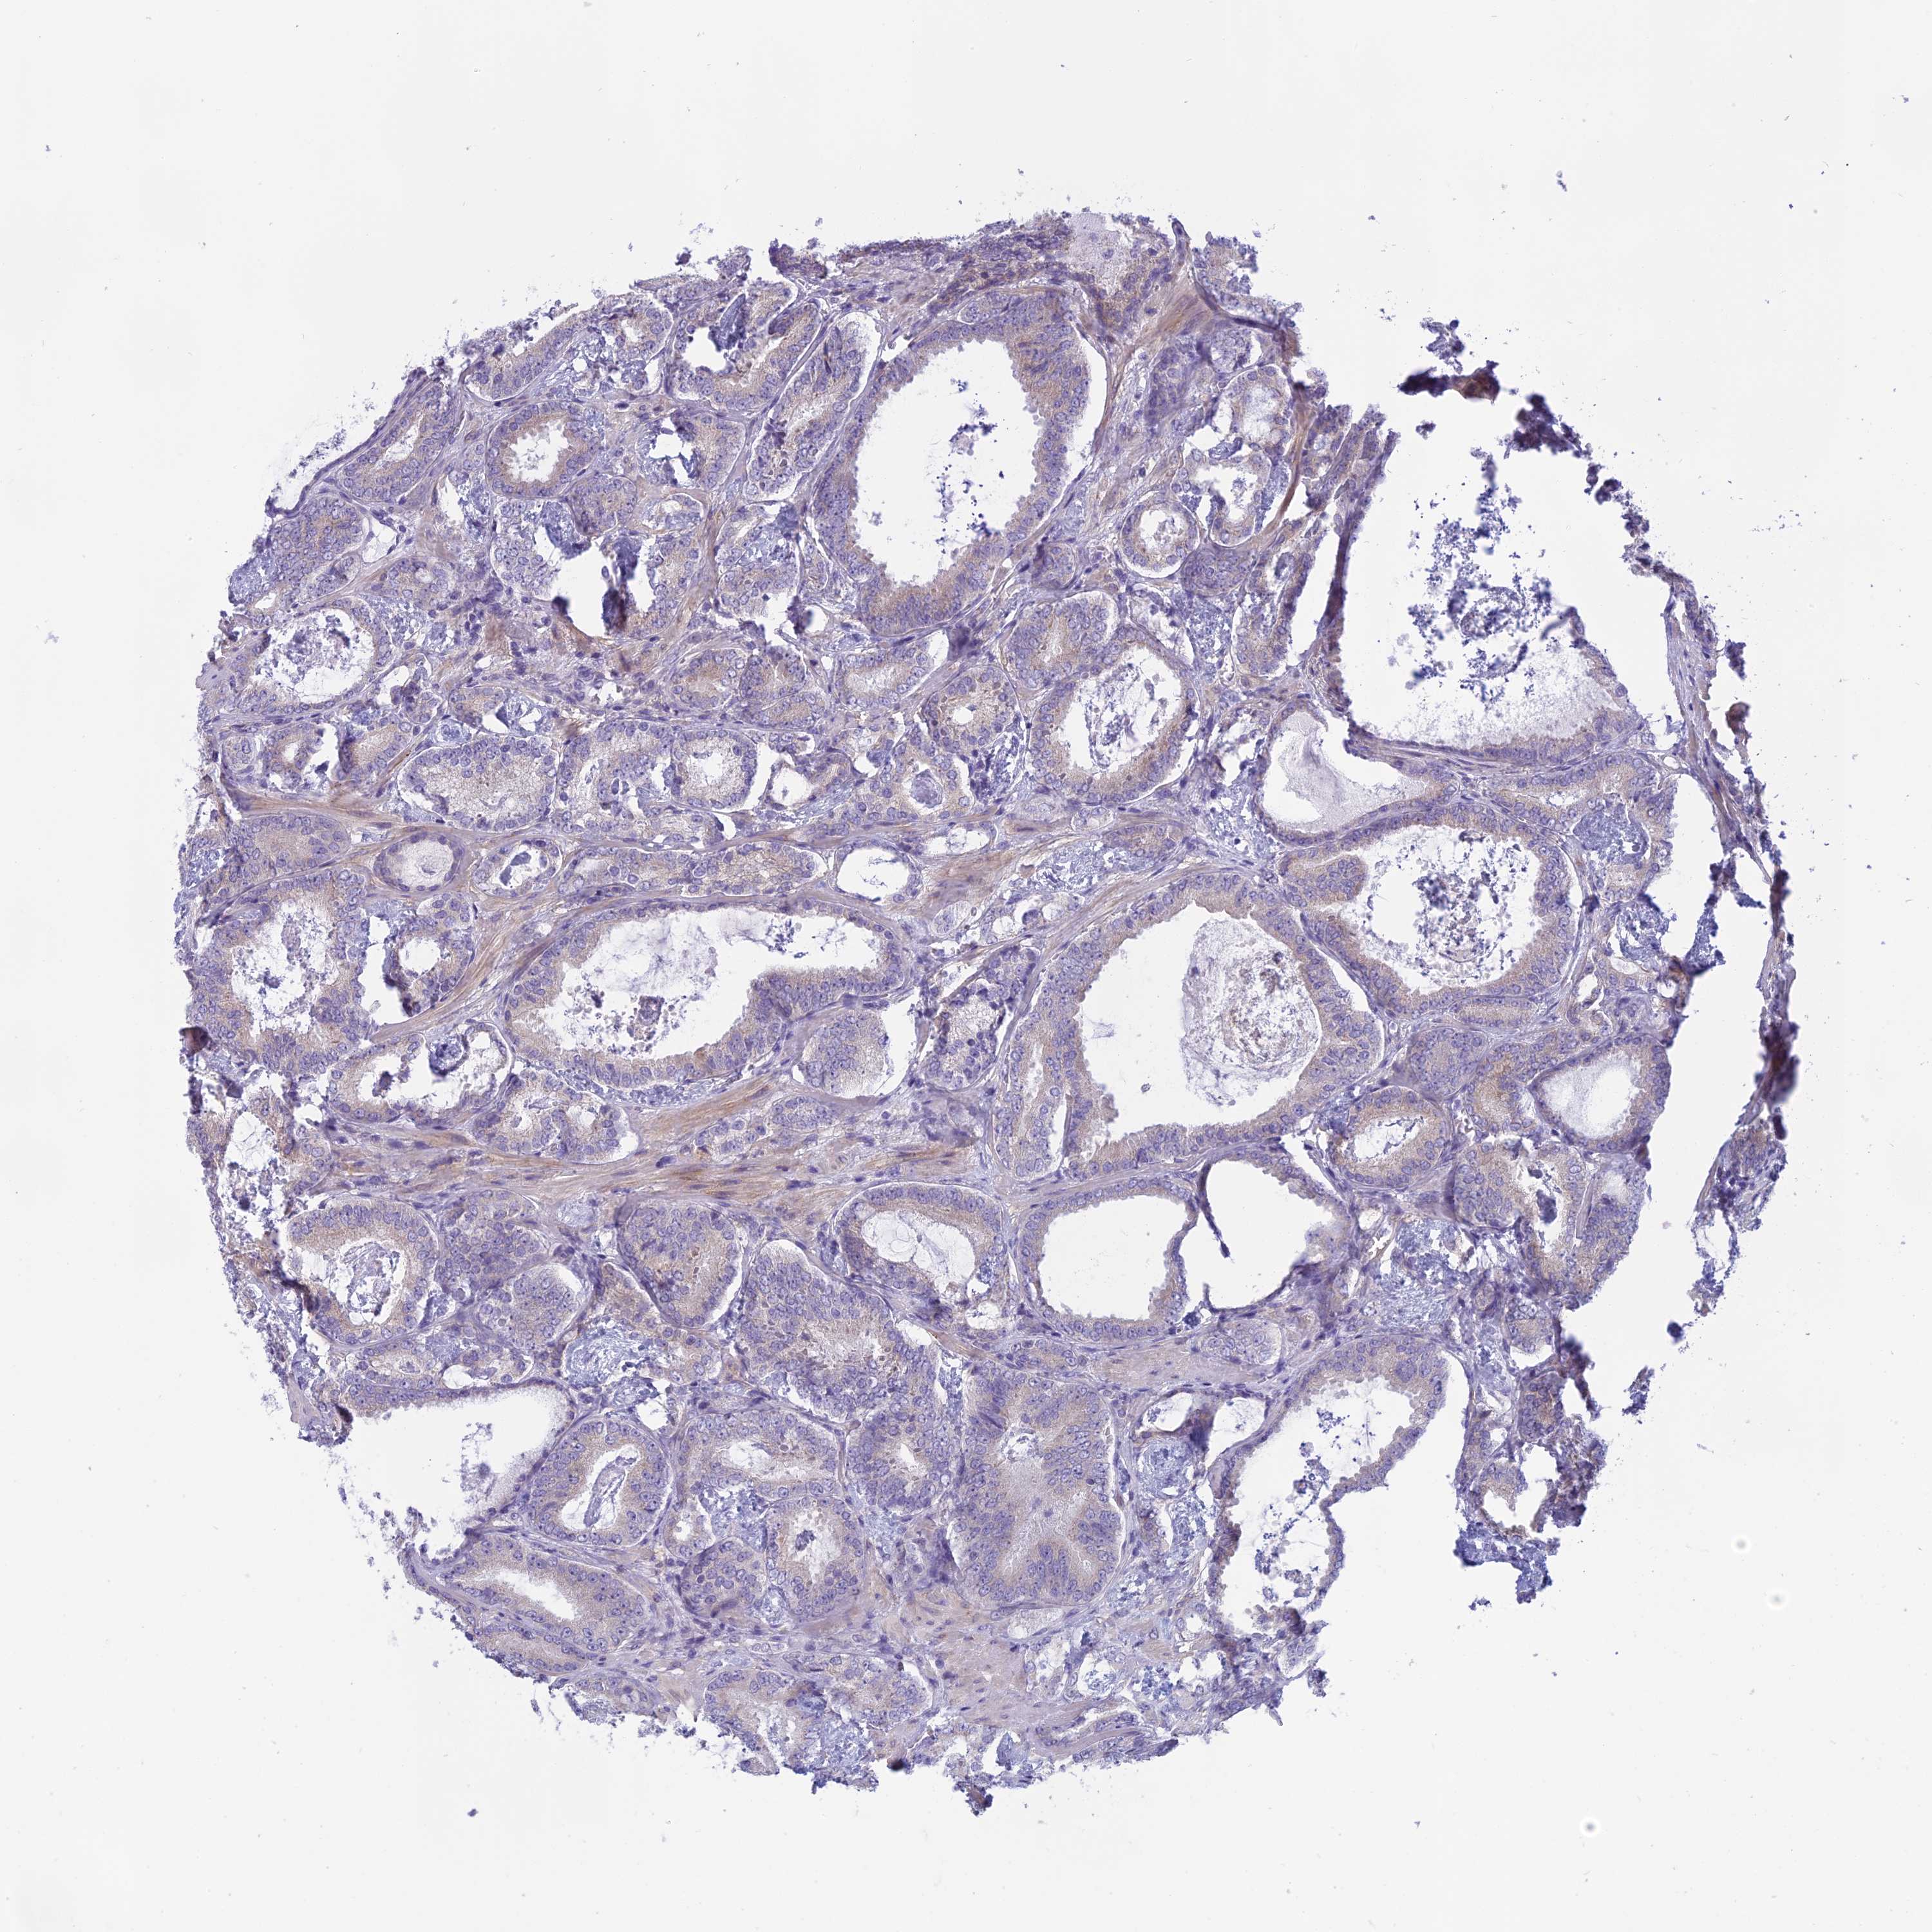

PROSTATE CANCER - Protein expressioni

A mouse-over function shows sample information and annotation data. Click on an image to view it in a full screen mode. Samples can be filtered based on level of antibody staining by selecting one or several of the following categories: high, medium, low and not detected. The assay and annotation is described here.

Note that samples used for immunohistochemistry by the Human Protein Atlas do not correspond to samples in the TCGA dataset.

Antibody stainingi

Antibody staining in the annotated cell types in the current human tissue is reported as not detected, low, medium, or high, based on conventional immunohistochemistry profiling in selected tissues. This score is based on the combination of the staining intensity and fraction of stained cells.

Each image is clickable and will lead to virtual microscopy that enables deeper exploration of all samples and also displays staining intensity scores, fraction scores and subcellular localization as well as patient and tissue information for each sample.

Antibody HPA043885

Antibody HPA053487

Staining

High

Medium

Low

Not detected

Intensity

Strong

Moderate

Weak

Negative

Quantity

>75%

75%-25%

<25%

None

Location

Nuclear

Cytoplasmic/membranous

Cytoplasmic/membranous,nuclear

Adenocarcinoma, NOS

Adenocarcinoma, High grade

Adenocarcinoma, Low grade